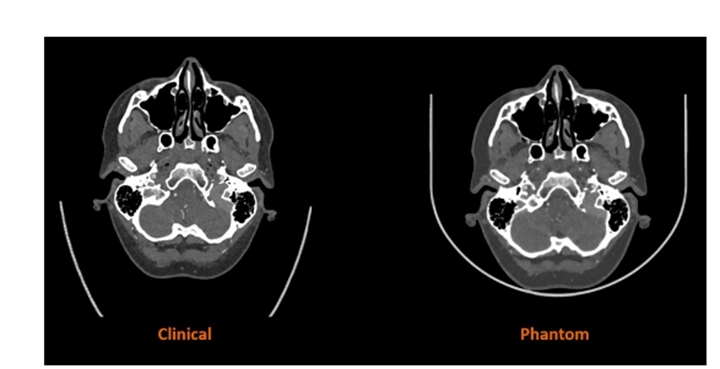

Stratasys擴(kuò)大醫(yī)學(xué)影像用防射線3D打印材料的應(yīng)用范圍

2025年12月8日,3D打印機(jī)OEM廠商Stratasys宣布可阻礙射線穿透的RadioMatrix 3D打印材料現(xiàn)已在美國全面上市。這種材料此前僅在有限范圍內(nèi)使用,如今可供醫(yī)療機(jī)構(gòu)、醫(yī)療器械制造商和研究機(jī)構(gòu)廣泛用于先進(jìn)的醫(yī)學(xué)成像、教育和培訓(xùn)等領(lǐng)域。據(jù)Stratasys公司聲稱稱,RadioMatrix是第一種也是唯一一種能夠精確控制放射阻射性的3D打印材料,可以創(chuàng)建在X射線成像下具有一致且可調(diào)可見性的患者特定模型。

Stratasys擴(kuò)大醫(yī)學(xué)影像用防射線3D打印材料的應(yīng)用范圍 7天前